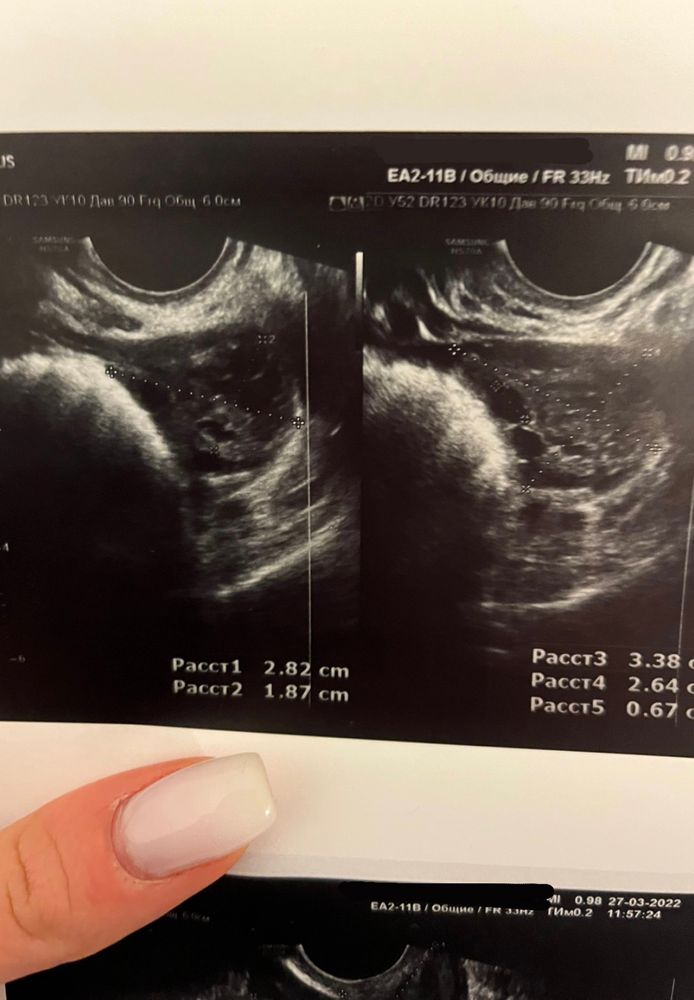

Здравствуйте! Ситуация следующая: с мужем начали практиковать ППА, потому что как говорится бояться уже нечего😂, но прямо планировать ещё рано, только начинаем вставать на ноги. Мы оба госслужащие, поэтому периодически проходим обследования общие, иногда сдаём кровь на ВИЧ, гепатиты. Поэтому за здоровье особо не переживали. М начались 4 марта, закончились 8 марта (всегда идут 4 дня). 3 ППА были с 11 по 13 марта, а 14 марта по моим ощущениям началась О. И вот где-то через неделю начинается самое веселое, частое чувство голода - то есть поем, а через 5 минут такое ощущение, что не ела неделю 🙈 усилилось обоняние, с каждым днём нарастало чувство слабости. Я уже думала, всё, ОНО😍😂 и за неделю (и 2 дня) до начала М начинает тянуть и подергивать левый яичник, иногда потягивает правый. Я пошла на узи малого таза…ожидала услышать что-то конкретное, но врачи сказали наблюдать дальше за состоянием и в случае задержки делать тест, а так, из того, что они увидели: что-то у меня там лопнуло (боюсь неправильно назвать) и произошло кровоизлияние в брюшную полость (большое темное пятно в нижней части, на снимке матки), а боль в левом яичнике обусловлена наличием в нем желтого тела. В общем как-то так. Сейчас уже 4-ый день задержки, левый яичник все также потягивает вечерами, сохраняется слабость и сонливость. Утром сегодня делала тест - кристально чистый, ни намёка на призрака. Подскажите, пожалуйста, в моем случае, я так понимаю, уже можно исключать беременность? Что это может быть? Фото снимков с УЗИ прилагаю (сделаны на 24 ДЦ). Заранее спасибо!